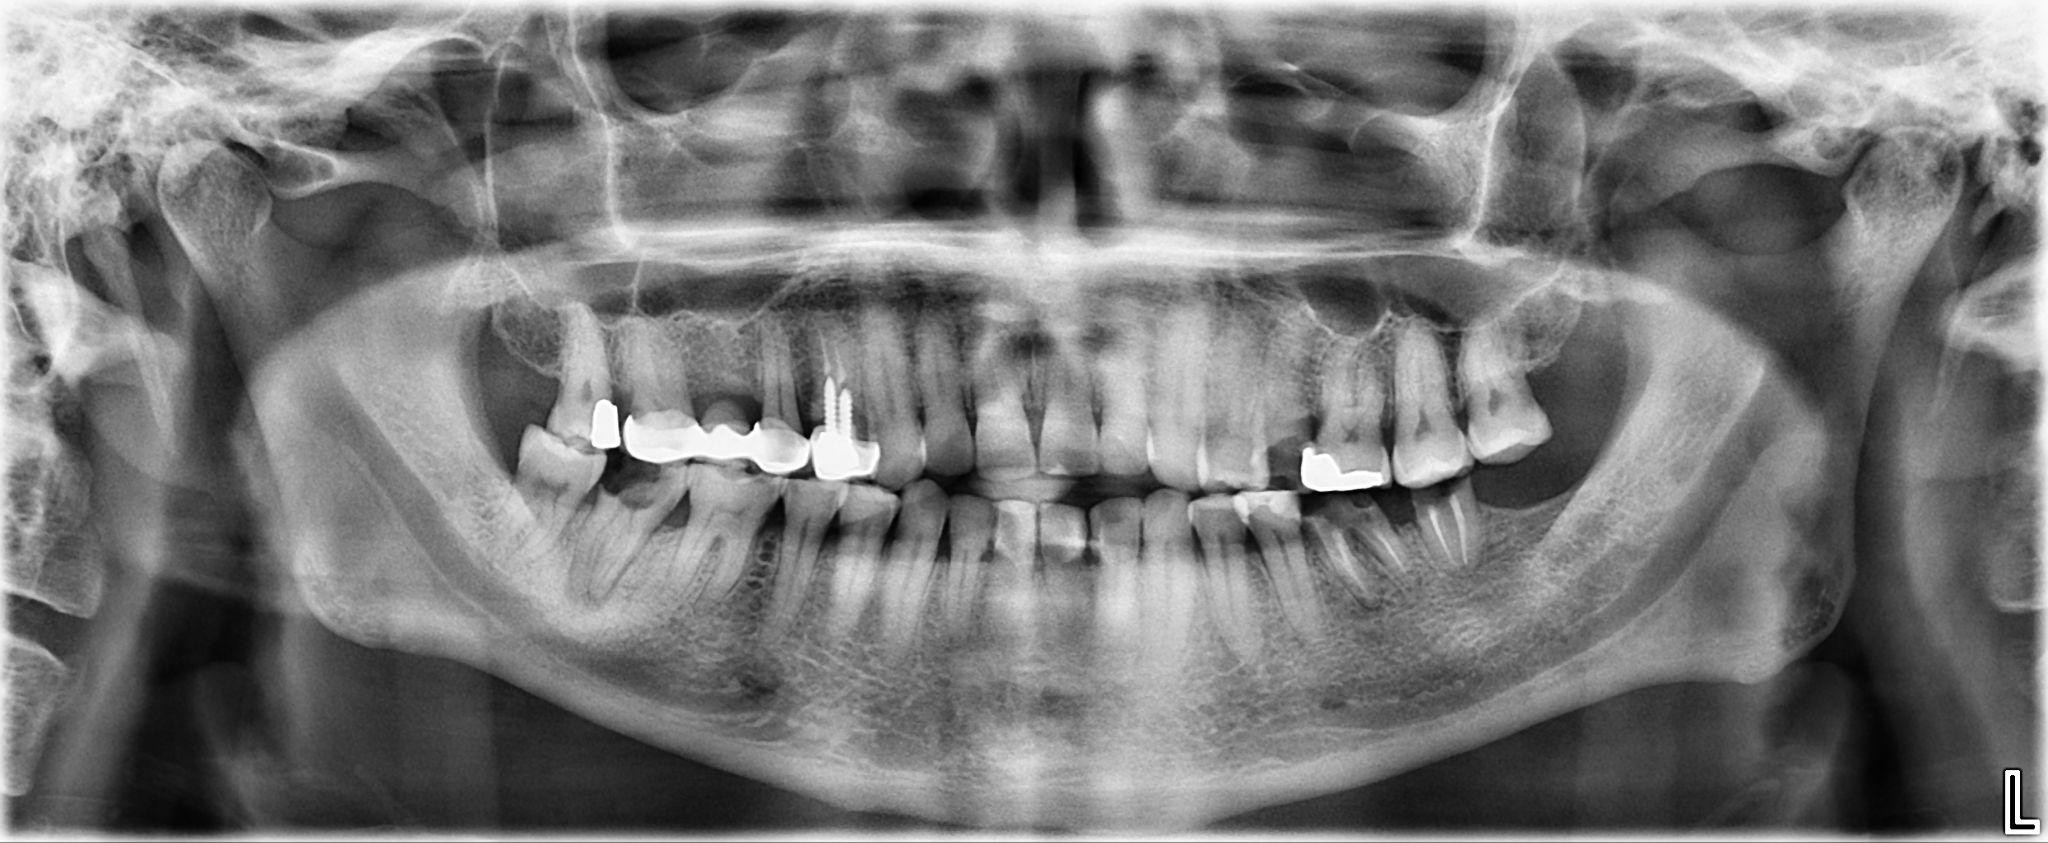

1. What option cannot be selected for the first quadrant of this panoramic X ray?

2. What option cannot be selected for the second quadrant of this panoramic X ray?

3. What option can be selected for the third quadrant of this panoramic X ray?

4. What option cannot be selected for the forth quadrant of this panoramic X ray?

5. What option cannot be selected for the first quadrant of this panoramic X ray?

6. What option cannot be selected for the third quadrant of this panoramic X ray?

7. What option cannot be selected for the forth quadrant of this panoramic X ray?

8. What option cannot be selected for the upper jaw of this panoramic X ray?

9. What option cannot be selected for the lower jaw of this panoramic X ray?

10. What option cannot be selected for the first quadrant of this panoramic X ray?

11. What option cannot be selected for the second quadrant of this panoramic X ray?

12. What option cannot be selected for the third quadrant of this panoramic X ray?

13. What option cannot be selected for the forth quadrant of this panoramic X ray?

14. What option cannot be selected for the upper jaw of this panoramic X ray?

15. What option cannot be selected for the lower jaw of this panoramic X ray?

16. What option cannot be selected for the upper jaw of this panoramic X ray?

17. What option cannot be selected for the lower jaw of this panoramic X ray?

18. What option cannot be selected for the upper jaw of this panoramic X ray?

19. What option cannot be selected for the lower jaw of this panoramic X ray?

20. What option can be selected for the upper jaw of this panoramic X ray?

21. What option cannot be selected for the lower jaw of this panoramic X ray?

22. What option cannot be selected for the upper jaw of this panoramic X ray?

23. What option cannot be selected for the lower jaw of this panoramic X ray?

24. What option cannot be selected for the upper jaw of this panoramic X ray?

25. What option cannot be selected for the lower jaw of this panoramic X ray?